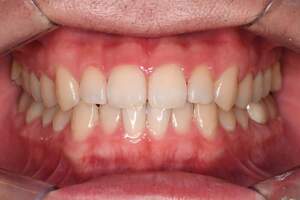

歯石除去・オフィスホワイトニング

治療前

治療後

| 年齢 | 30歳・女性 |

| 主訴 | クリーニング・歯を白くしたい |

| 治療内容 | 歯石除去・オフィスホワイトニング |

| 治療期間 | 60分×2回 |

| 費用 | 歯石除去 約2,000円 オフィスホワイトニング2回 6,600円(自費 診療) |

| リスク・副作用 | ・歯ぐきの炎症が強いと歯石を取る際に出血することがあります ・歯と歯の間に隙間ができるので、息が漏れ発音しにくいと感じることがあります ・歯ぐきの炎症が軽減すると歯ぐきが引き締まり、歯が長く見えることがあります ・ホワイトニングの効果は永久的なものではなく徐々に色戻りが起こります ・ホワイトニング後は歯の表面の水分量が一時的に少なくなりしみることがあります ・ホワイトニングは自費診療の施術です |